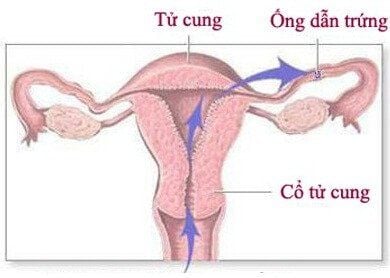

Lạc nội mạc tử cung là một bệnh phụ khoa phổ biến, tuy lành tính nhưng bệnh vẫn gây nhiều khó chịu và cảm giác đau đớn cho bệnh nhân, thậm chí có thể dẫn đến vô sinh ở phụ nữ.

Nguyên nhân gây lạc nội mạc tử cung vẫn chưa được xác định rõ, do đó, mục tiêu của việc điều trị nhằm kiểm soát các triệu chứng. Dựa trên triệu chứng và mong muốn có thai trong tương lai của bệnh nhân, bác sĩ sẽ đề xuất phương pháp điều trị thích hợp.